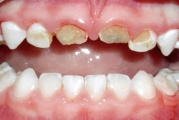

Fluoroosi

Fluoroos